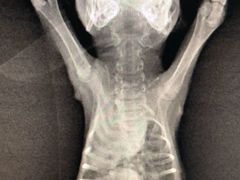

• 爱侣宠医·鹦鹉专科·小型哺乳类·异宠专科(灵石路店)

• 其他(161)»